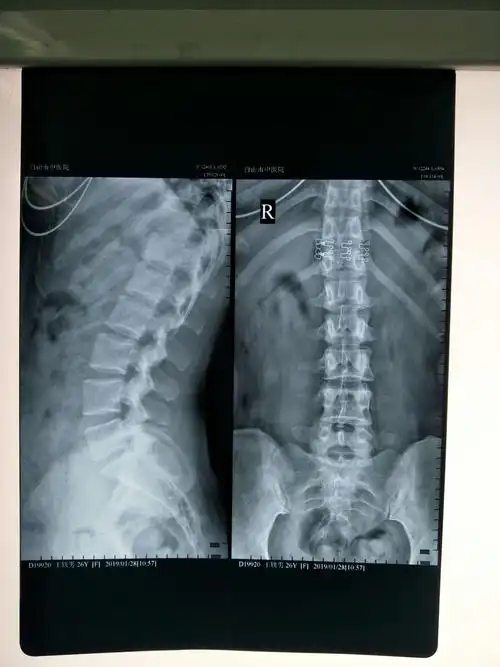

白山市中医院骨伤一疗区行腰椎间盘射频热凝消融术微创手术